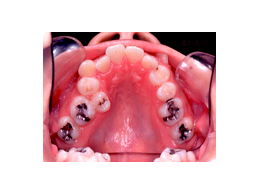

叢生 治療後 上顎

歯を抜いたスペースを利用して、残りの歯をきれいに並べ替えてゆきます。この患者さんの場合は、抜いたスペースはほとんど余りませんので、意外に早く治療が終わりました。

この患者さんでは、上下左右の歯を計4本抜きましたが、それでももスペースが足りませんので、さらに顎の形を変えて並べ替えました。

抜歯する歯は、変なところに生えていた犬歯ではなく、4番目の歯(=第一小臼歯)です。犬歯を抜くと、顎運動や歯並びの見た目、口元のふくらみがなくなることで老けて見えるなど、いろいろな悪影響があります。従って、できるだけ抜歯は避けたいのです。